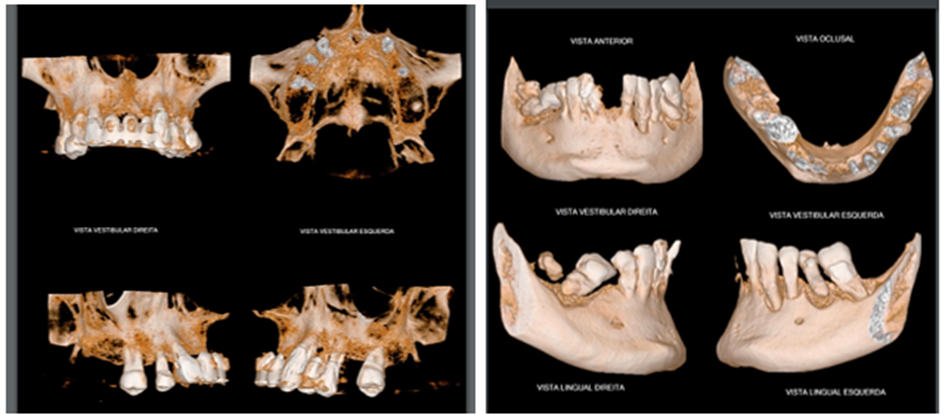

Paciente procurou tratamento protético reabilitador com queixa de dentes abalados e com mobilidade, mau hálito e sangramento gengival. Após exame clínico, radiográfico e tomográfico constatou-se a necessidade de exodontia de todos os dentes remanescente e instalação de implantes na maxila e mandíbula para posterior confecção de duas próteses do tipo Protocolo de Brånemark – prótese total fixa implantossuportada sobre implantes Maestro CM da Implacil De Bortoli, pilares do tipo mini-cônicos, barra metálica e prótese de resina acrílica, cuja abordagem encontra-se no dia a dia dos consultórios dentários.

Diante dos exames foi proposto ao paciente a extração de todos os dentes remanescentes, instalação de implantes na maxila e mandíbula e duas próteses totais provisórias durante o período de osseointegração.